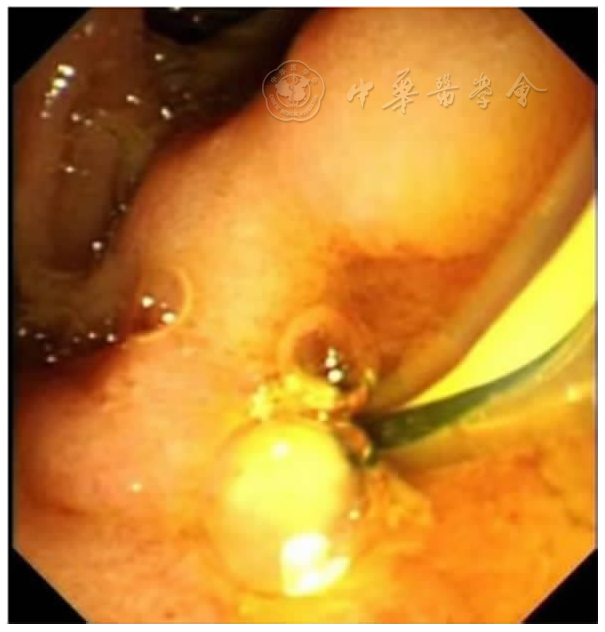

患者男,71岁。主因"右上腹痛伴黄疸1月"于2022年3月11日收入保定市第一中心医院消化内三科。患者1月前无明显诱因出现右上腹部疼痛,呈持续性钝痛,并向肩背部放射,伴发热,体温维持在37.8℃左右,以午后为重,伴寒战、皮肤及小便发黄、偶有恶心、无呕吐、体重下降约2.5 kg。既往19年前因"胆管结石"行"胆总管切开取石及胆道镜下肝内胆管取石术";1年前又因"胆囊结石"行"胆囊切除术"。入院查体:T 37.6℃、P 70次/分、R 17次/分、BP 120/80 mmHg,神志清楚、精神差、结膜无苍白、巩膜黄染、周身浅表淋巴结未触及肿大、心肺查体无异常、腹平软、上腹部可见手术疤痕,有压痛、无反跳痛及肌紧张、肝脾肋下未触及、肝区叩击痛阳性、移动性浊音阴性、肠鸣音正常。入院后辅助检查:血常规:白细胞7.70×109/L、血红蛋白117.00 g/L、血小板226.00×109/L、中性粒细胞比率72.20%;肝功:丙氨酸氨基转移酶46.60 U/L、天门冬氨酸氨基转移酶41.10 U/L、白蛋白36.90 g/L、总胆红素52.60 μmol /L、直接胆红素36.00 μmol/L、间接胆红素16.60 μmol/L、γ-谷氨酰转肽酶620.00 U/L、碱性磷酸酶337.20 U/L;肿瘤标记物:AFP 2.02 ng/ml、CEA 1.62 ng/ml、CA-19927.26 IU/ml;门诊上腹部CT提示:肝左叶体积小;胆总管下段高密度影,结石?考虑低位胆道梗阻。初步诊断:胆总管结石伴化脓性胆管炎。给予抗感染、保肝、抑酸、补液等支持治疗。于2022年3月14日经内镜中心行经内镜逆行胰胆管造影术(endoscopic retrograde cholangiopancreatography,ERCP)取石,术中泛影葡胺造影可见胆总管扩张1.2 cm,下端约见1.0 cm充盈缺损影,胆总管上段不规则充盈缺损影,肝内胆管未见异常,弓形电刀沿乳头11点方向切开约0.3 cm,1.2 cm扩张球囊扩张乳头,取石网篮取出黄褐色结石及黄白色脓性分泌物(图1),术后置入鼻胆引流管,胆汁引流通畅。术后给予暂禁食水、抑酸、补液等综合治疗。患者仍感腹痛,体温最高达38℃,术后第3天复查腹部CT示:ERCP术后改变,肝内胆管扩张;肝顶稍低密度。当时考虑患者腹痛为鼻胆管刺激所致,遂予拔除。复查血常规及肝功能较术前无明显变化,C反应蛋白:37.30 mg/L、血淀粉酶及脂肪酶正常,考虑胆管内感染脓液引流不畅,于3月21日再次行ERCP术:术中胆管造影仍提示胆总管内不规则充盈缺损影,用取石球囊取出大量黄白色脓性分泌物(图2),术毕置入8.5Fr-8 cm塑料胆管支架(图3)。术后患者腹痛仍不能缓解,并出现持续高热,体温最高达38.9℃,抗生素升级为比阿培南0.3 g,12 h 1次静脉点滴。同时口服熊去氧胆酸胶囊250 mg,每日3次,监测肝功能及炎症指标。3月24日行上腹增强CT示:肝顶多发异常强化,考虑肝脓肿可能(图6)。因治疗效果不佳,请感染性疾病科会诊后仍建议继续抗感染治疗,监测炎症指标及脓肿影像学变化,尽可能穿刺引流以缩短病程,并留取血培养以明确致病菌。遂调整比阿培南0.3 g,8 h 1次、加用莫西沙星0.4 g,每日1次联合抗感染,同时加用人血白蛋白支持对症治疗。患者腹痛及发热症状仍无明显缓解,3月31日进行上腹MRI平扫+增强检查提示为肝内多发异常信号,肝内外胆管及胆总管扩张,肝门区胆管截断,肝门区淋巴结肿大(图7)。复查腹部彩超提示肝脓肿,液化不明显,不易穿刺。于2022年4月6日加用去甲万古霉素抗感染治疗,患者治疗效果欠佳。再次请普外科会诊,仔细阅片考虑肝门区胆管截断,肝内多发不均低密度,不除外恶性肿瘤可能,建议穿刺活检。超声造影提示肝内不均质回声,倾向炎性病变,因周边血管丰富穿刺出血风险高,不宜进行穿刺活检。此时患者内科保守治疗效果不佳,恶性肿瘤不能除外,经与患者及家属反复沟通,建议手术治疗,于4月4日转入普外科并行手术探查,术中发现肝左叶萎缩、质硬,多发肿物突出肝表面,右肝未见明显肿物,腹腔广泛粘连,肝门部多发肿大淋巴结,术后病理证实为左半肝低分化胆管细胞癌(图8)。患者术后腹痛好转,体温恢复正常,家属拒绝进一步治疗,自动出院,离院后1个月病逝。

图5 3月21日ERCP下左半肝肝内胆管不显影,肝门部胆管截断